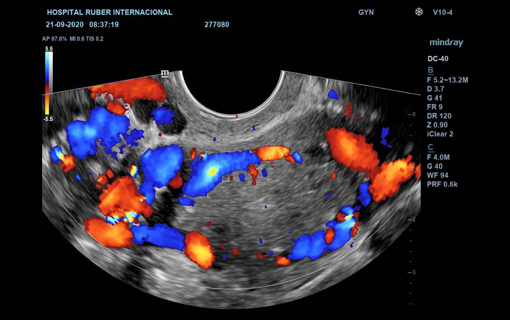

Doppler color: es la más utilizada, permite ver el flujo de sangre que pasa por los vasos en el estudio. En caso de que la sangre se aproxime a la sonda, se suele representar de color rojo, y si se aleja, de color azul.